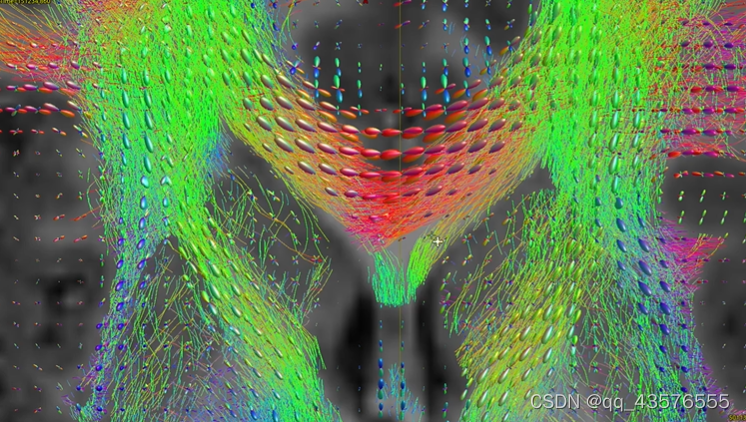

maskfilter: [100%] applying dilate filter to image -生成弥散张量dt.mif,可用mrview查看,每个体素有六个值(描述一个椭圆体),标志着水分子的弥散方向,用椭球方向标志纤维的走向,用FA值衡量各向异性,各向异性越大,FA值越大

tensor2metric: [100%] computing metrics由于弥散像体素比纤维大得多,无法反映神经纤维束的真实走向,这里我们不用dt.mif估算神经的方向,因此使用constrained spherical deconvolution(CSD)算法,计算各个方向纤维束的贡献,这里的kernel称为反应函数

dwi2response: Deleting scratch directory (/home/hzhb/Fengz/demo/dwi2response-tmp-MWHD2Y/)得到反应函数后,我们估算FOD,该步骤大概需要几分钟,可以用mrview查看得到的文件dwi_gmCsd.mif等,得到每个体素的不同纤维走向的贡献程度(可能性大小)

dwi2fod: [100%] performing MSMT CSD (3 shells, 3 tissues) 下面用FOD进行神经纤维束的追踪,把一个个相连体素的方向画线,这就完成了纤维束的追踪。可以选择全脑的追踪和兴趣区域的追踪。

下面用FOD进行神经纤维束的追踪,把一个个相连体素的方向画线,这就完成了纤维束的追踪。可以选择全脑的追踪和兴趣区域的追踪。